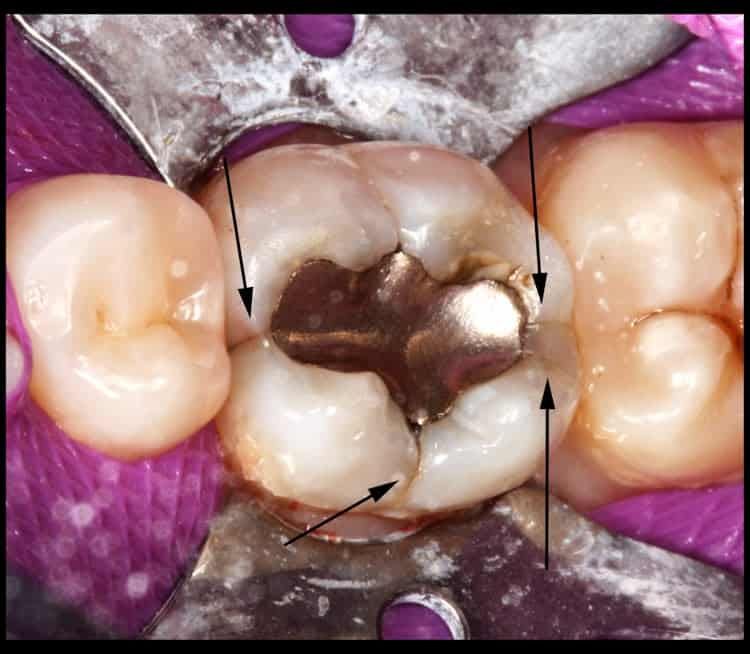

Research tells us that teeth with tooth-colored (composite resin) fillings crack just as often as those with silver fillings. My experience over 15 years, however, tells me that teeth with LARGE silver fillings crack much more frequently than with composite fillings. But even the bonding process can’t stop a crack from forming if the stress isn’t relieved. I’d like to show you some examples of what we often see:

It does seem that these cracks form around old fillings most of the time……..but they can even happen in teeth that have never had any work done. All it takes is a lot of force (usually grinding and/or clenching your teeth) and enough time. Here’s an example from a young man in his late 30’s who clenches his teeth so hard that he split this back molar completely in 1/2. It had NEVER had any dental work, and in fact, it didn’t even have a cavity. But he split it so far that it had to be extracted. Obviously I recommended a nightguard to help him not do this to any other teeth!